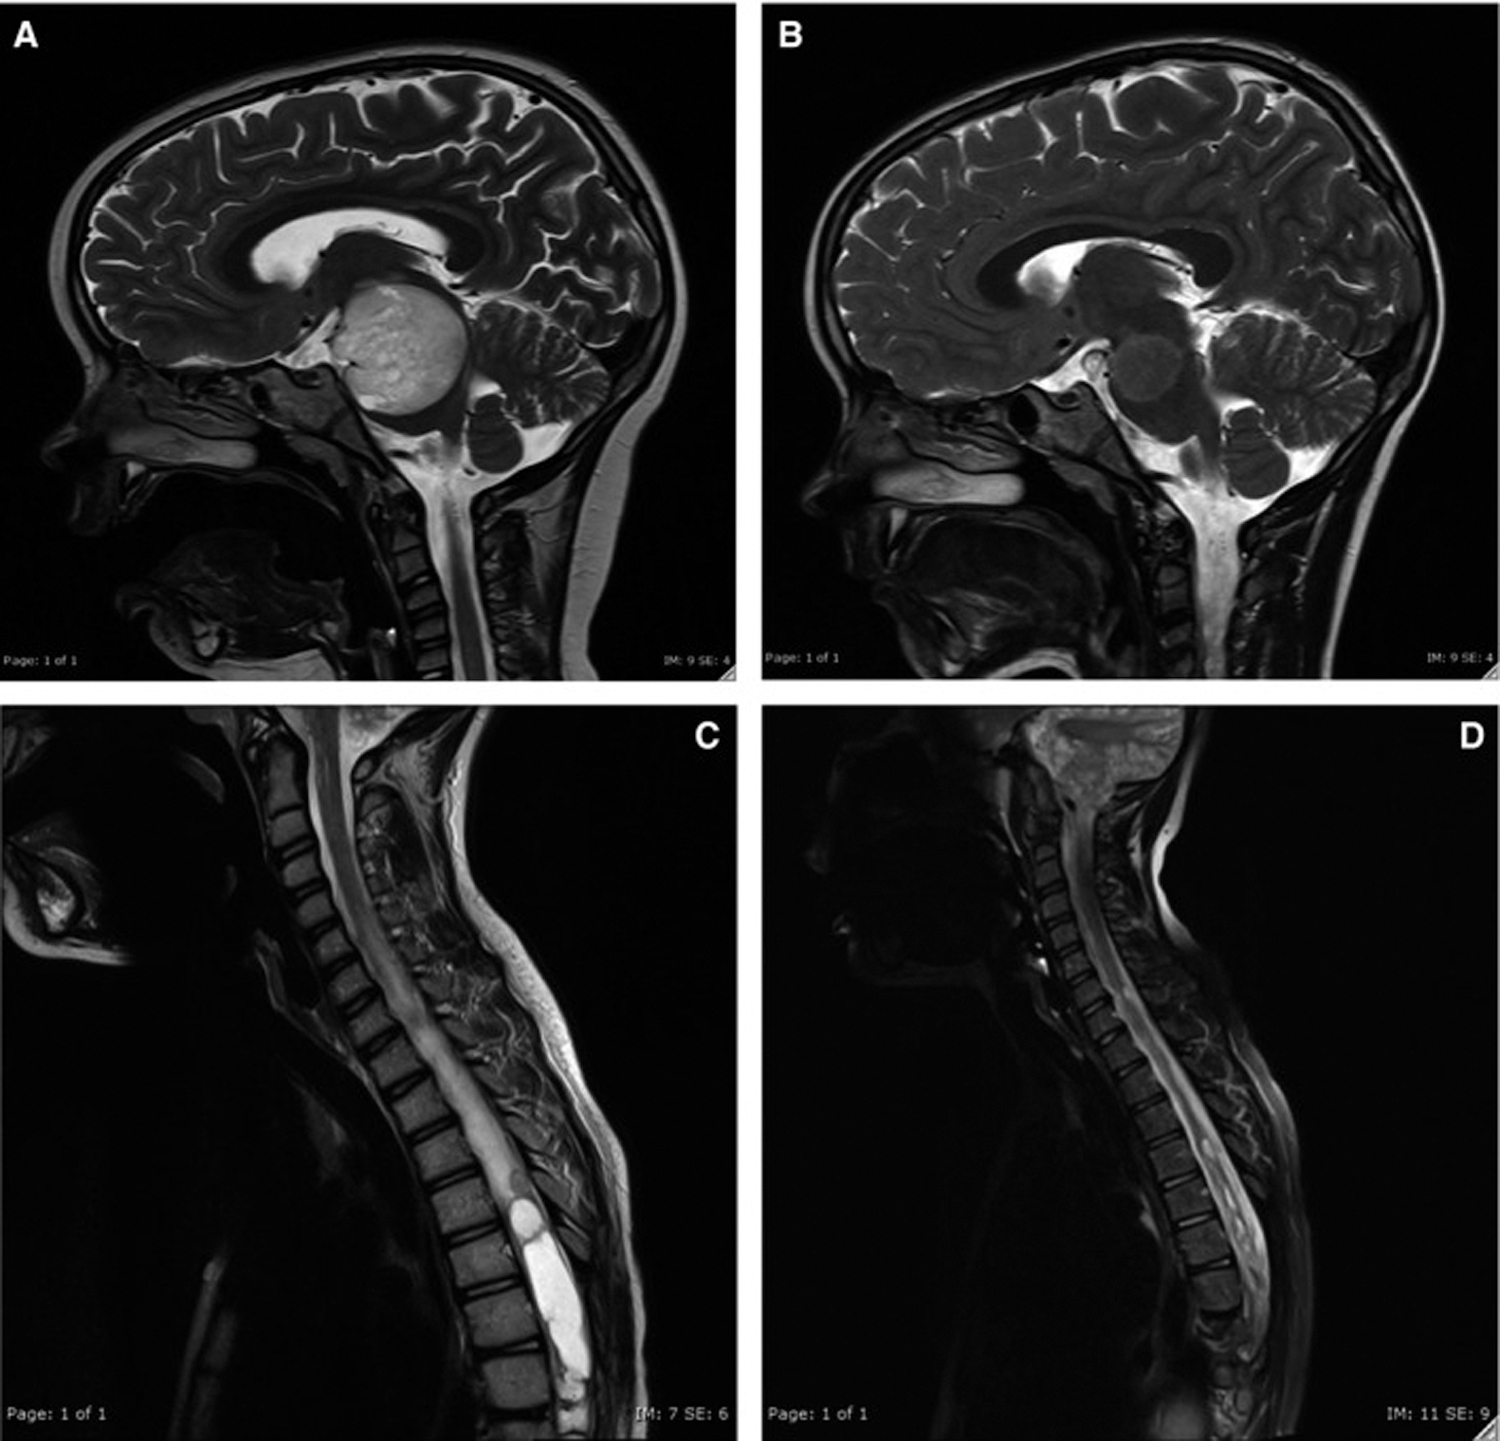

Targeted therapy uses drugs to target specific genes and proteins that are involved in the growth and survival of cancer cells, one example is bevacizumab that is used to treat low-grade gliomas (Zhukova et al., 2019) (Fig. 1). Genomic techniques started to elucidate the pathogenesis of many pediatric brain tumors, however, there are some challenges that limit the translation of these findings into therapy (Kumar et al., 2018; Chalmers et al., 2017; Grobner et al., 2018; Northcott et al., 2017). The majority of pediatric brain tumors resist genomic targeted treatments. In addition many pediatric brain tumors are characterized by deviant epigenetic landscapes, and there is no effective way to specifically target these changes (Capper et al., 2018).

Figure 1: Radiological response to bevacizumab therapy; MRI imaging at baseline PLGG (A) and PLGG10 (C) and 15 mo after completion of therapy PLGG8 (B) and after 6 mo of therapy PLGG10 (D) (Zhukova et al., 2019).